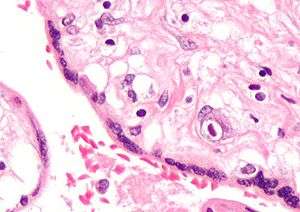

Development

The placenta begins to develop upon implantation of the blastocyst into the maternal endometrium. The outer layer of the blastocyst becomes the trophoblast, which forms the outer layer of the placenta. This outer layer is divided into two further layers: the underlying cytotrophoblast layer and the overlying syncytiotrophoblast layer. The syncytiotrophoblast is a multinucleated continuous cell layer that covers the surface of the placenta. It forms as a result of differentiation and fusion of the underlying cytotrophoblast cells, a process that continues throughout placental development. The syncytiotrophoblast (otherwise known as syncytium), thereby contributes to the barrier function of the placenta.

Micrograph of CMV placentitis.

Micrograph of CMV placentitis. A 3D Power doppler image of vasculature in 20-week placenta